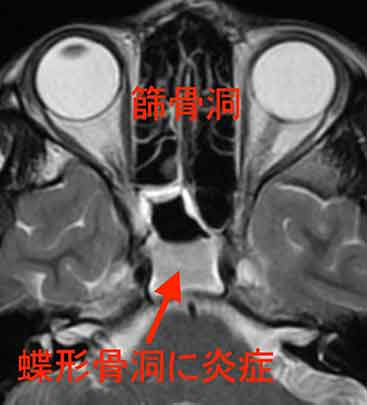

MRI検査を行っところ、

蝶形骨洞という場所に感染を起こして膿が貯まっている状態で、急性副鼻腔炎(蝶形骨洞炎)と診断しました。

顔面の骨の裏側には副鼻腔という空洞が拡がっており、鼻腔(鼻の穴)と細い穴でつながっています。風邪や花粉症で粘膜の炎症が起きると、この細い穴がふさがり、内部に細菌が繁殖して膿が貯まった状態が急性副鼻腔炎です。頭を下げると、副鼻腔内部の圧力が上昇して頭痛が強くなります。1)

この症例のような蝶形骨洞の副鼻腔炎は奥深い場所のため、レントゲン検査では分かりにくく、MRI検査で初めて診断が付く事があります。

重症の急性副鼻腔炎では、細菌感染が頭蓋骨内部まで及んで命に関わる場合もあるので注意が必要です。